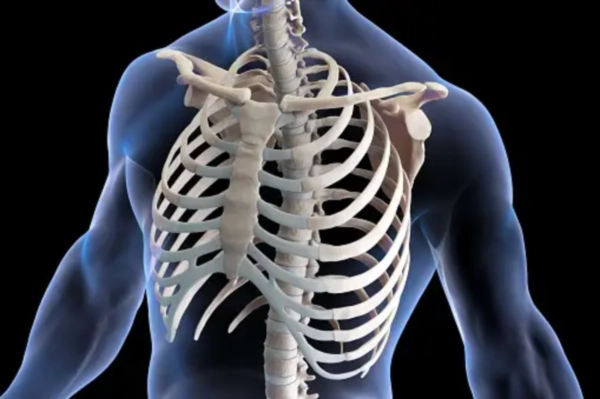

왼쪽 갈비뼈 아래 통증은 많은 사람들에게 발생할 수 있는 문제로, 여러 가지 원인에 의해 나타날 수 있습니다. 정확한 원인을 찾기 어려워 고생하시는 분들이 많으신데요, 이러한 통증은 가벼운 불편함에서부터 심각한 질병의 증상까지 다양하게 나타날 수 있으며, 정확한 원인을 파악하는 것이 중요합니다. 이번 글에서는 왼쪽 갈비뼈 아래 통증의 주요 원인, 증상, 예방 방법, 그리고 치료 방법에 대해 자세히 알아보겠습니다.

왼쪽 갈비뼈 아래 통증은 소화기 계통, 심혈관 질환, 근골격계 문제, 그리고 신경계 질환 등 다양한 원인에 의해 발생할 수 있습니다. 이를 예방하고 치료하기 위해서는 정확한 진단과 적절한 치료가 필요합니다.

왼쪽 갈비뼈 아래 통증의 주요 원인

소화기 계통의 문제는 왼쪽 갈비뼈 아래 통증의 흔한 원인 중 하나입니다. 이 부위에는 위, 비장, 췌장 등이 위치하고 있어 이들 기관의 이상이 통증을 유발할 수 있습니다.